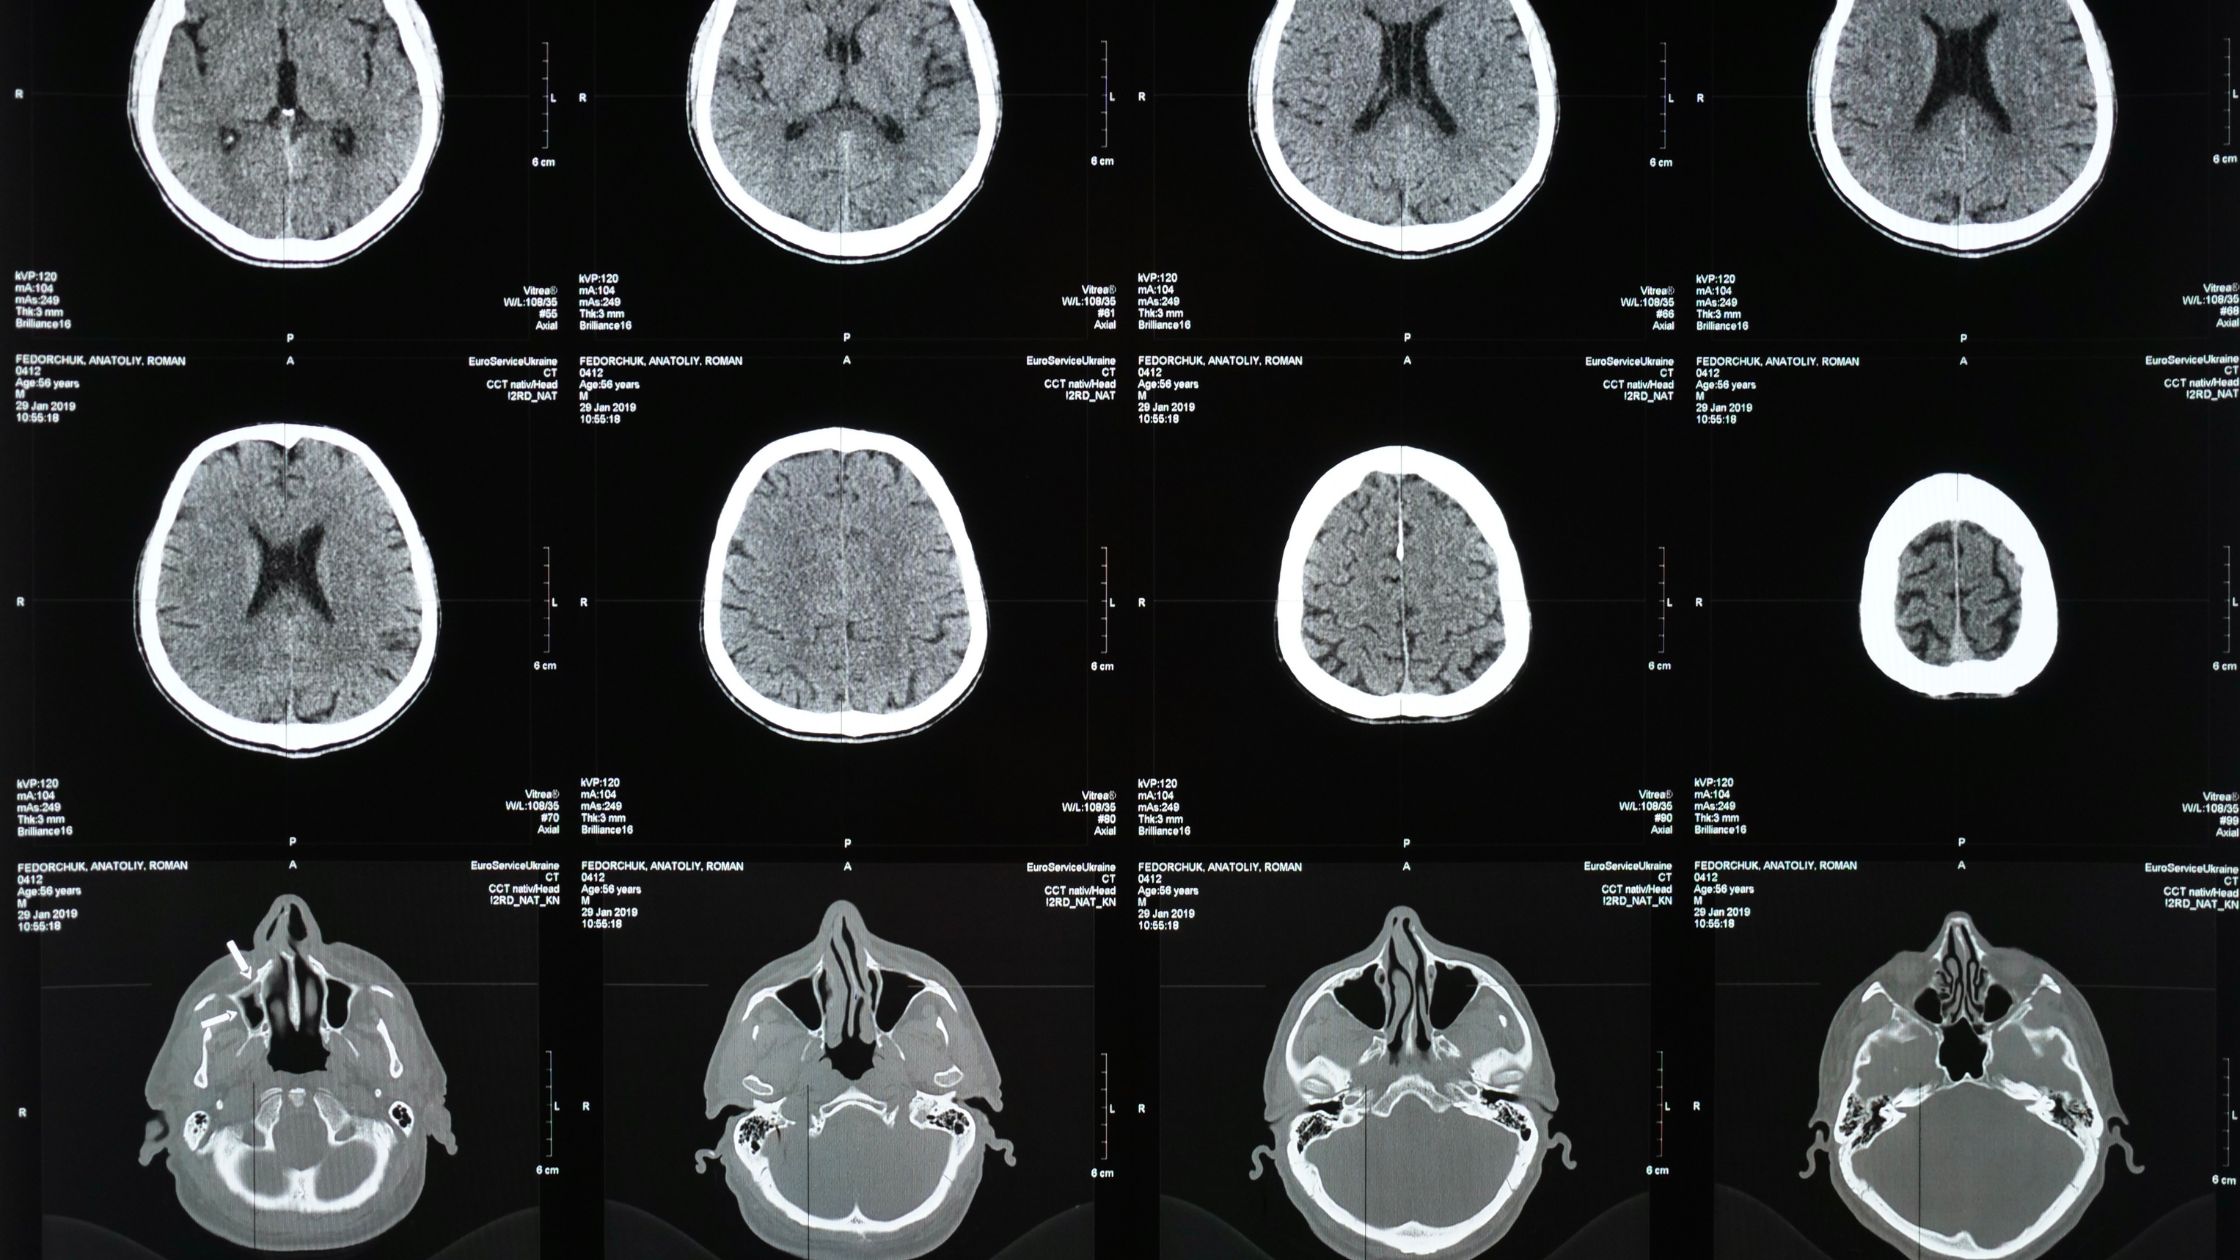

Infartos talámicos mediales bilaterales, un hallazgo típico debido a la oclusión de la arteria de Percheron